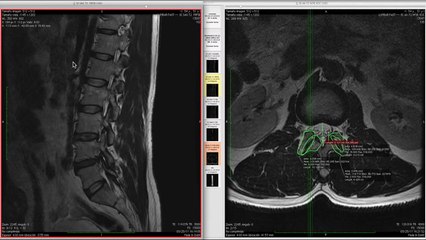

La imagen por resonancia magnética, abreviado como IMR, es un procedimiento no invasivo que permite obtener imágenes del interior del cuerpo sin utilizar radiación. Se emplea para el tratamiento de una amplia variedad de enfermedades. Te invitamos a conocer en detalle de qué se trata.